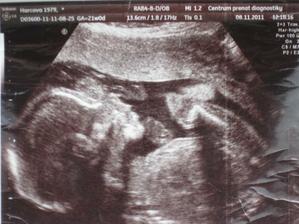

Druhé Pařezátko je Agátka

Druhé miminko čekáme kolem 20. března - je to naše druhé překvapení z bříška a jsme moc napnutí co to bude 🙂

Ve 40.týdnu se nám v kyjovské porodnici 22.3.2012 v 3:46hod narodila dcera Agátka 3,30kg a 52cm. Jsme moc rádi, že se nám povedla holka a máme doma páreček.